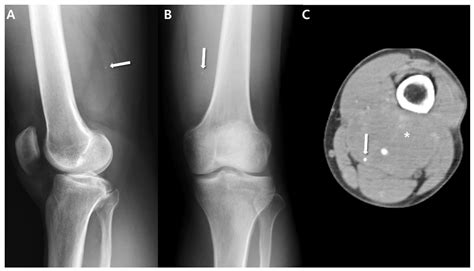

• Bone Sarcomas (Osteosarcomas): These originate specifically within the bone tissue. While they are distinct from bone metastases (cancers that have spread to the bone from other organs), they are considered primary bone cancers.

• Persistent bone pain that may worsen at night or during physical activity.

Once a doctor suspects a sarcoma, they will utilize a combination of diagnostic tools to confirm the diagnosis and determine the extent of the disease. The journey to a diagnosis usually involves imaging tests, such as X-rays, MRIs, or PET scans, which help identify the exact location and size of the tumor. A biopsy—where a small sample of the tissue is removed and examined under a microscope—is the gold standard for confirming exactly what is a sarcoma in a specific patient.